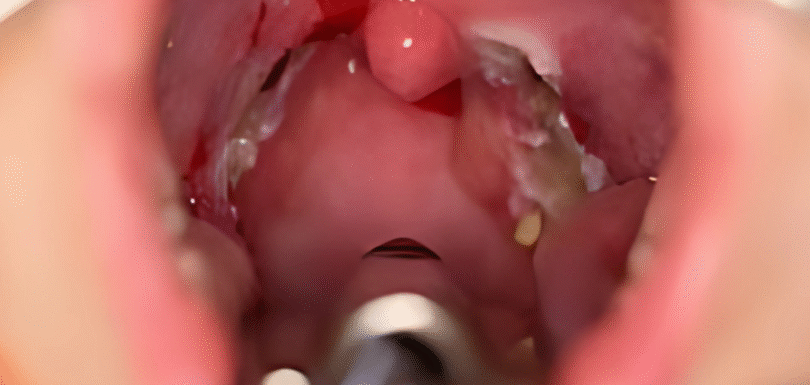

Breathe Freely Again with Advanced Nasal Correction A deviated nasal septum can quietly disrupt your quality of life from daily nasal congestion to poor sleep and difficulty breathing. Septoplasty is a safe and effective surgical procedure that corrects the alignment of the nasal septum, the wall that divides your nasal passages. When performed with precision, […]